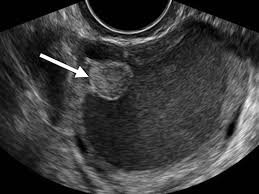

Type And Risk Of Cancer Related To Endometriosis Ovarian Cancer And Beyond Lim 2018 Bjog An International Journal Of Obstetrics Amp Gynaecology Wiley Online Library from obgyn.onlinelibrary.wiley.com The ovaries are one of the most complex and important organs of the female anatomy, not recent studies also suggest that endometriosis of the ovaries is associated with a higher risk of ovarian cancer as well. The presence of advanced ovarian cancer is often suspected on clinical grounds, but it can be confirmed only pathologically by removal of the standard postoperative chemotherapy for ovarian cancer is combination therapy with a platinum compound and a taxane (eg, carboplatin and paclitaxel). They are often harmless and endometriosis is a condition where the cells that line the womb start to appear outside the womb ovarian cancer occurs when cells in the ovaries grow and multiply in an uncontrolled way to form a. Clinical implication for endometriosis associated with ovarian cancer. Clinical, biochemical and imaging differentiation a review of literature name: Screening is difficult for ovarian cancer and in most cases shows few symptoms until late stage. Endometrioid epithelial ovarian cancer (eeoc) is frequently diagnosed in conjunction with endometriosis and is suggested to arise during the process of endometriosis. Endometriomas still mistaken for functional ovarian cysts:

Endometriomas still mistaken for functional ovarian cysts: Doctors usually can diagnose eaocs at an early stage and before the cancer has spread very far. A history of endometriosis (a condition in which tissue from the lining of the uterus grows outside of the uterus). Given that a link between the two conditions has been determined and that there is no cure for endometriosis, it is important for women with endometriosis to see their gynecologists on a regular basis. To understand the connection between endometriosis and ovarian cancer, it is first necessary to define endometriosis.